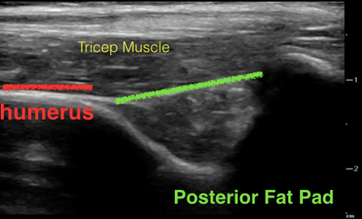

Normal Ultrasound

Longitudinal

In an elbow without injury, the fascial line that connects bony prominences in the olecranon fossa is flat and slightly below each bony ridge.